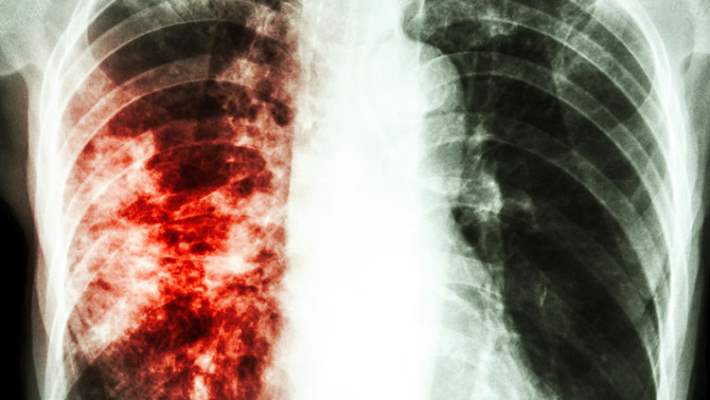

Tüberküloz bir bakterinin sebep olduğu, akciğerlerde başlayan ve tüm vücudu etkileyebilen bir enfeksiyondur. Bakteri bir kere vücuda girdikten sonra uzun bir süre boyunca herhangi bir belirtiye yol açmayabilir. Vücuda ilk girişinde neden olduğu enfeksiyonsa bağışıklık sistemi tarafından bastırılabilir. Ancak bakteri bedenimizde gizli bir şekilde bekler ve daha sonra aktif tüberküloz hastalığı başlar. Bu evrede esas belirtiler görülür ve hastalık diğerlerine de bulaşabilir. Peki tüberkülozun risk faktörleri nelerdir?

Aktif hastalığın belirtileri arasında inatçı bir öksürük, sürekli bitkinlik, kilo kaybı, iştah kaybı, yüksek ateş, öksürürken kan gelmesi ve geceleri terleme şikâyeti mevcuttur. Bu belirtiler başka hastalıklardan da kaynaklanabileceği için kişi tüberkülozdan şüphelenmeyebilir. Ancak eğer çevrenizde biri yakın zamanda hastalığı geçirdiyse ve belirtileri kendinizde görüyorsanız mutlaka bir sağlık uzmanına görünmelisiniz.

Tüberküloz bakterisinin bulaştığı herkeste aktif tüberküloz hastalığı görülmez. Bağışıklık sisteminin zayıflamış olması aktif tüberkülozun risk faktörleri arasındadır. Bu kişilerde ayrıca tüberkülozun akciğerlerden çıkıp lenf nodüllerine ve vücudun diğer bölümlerine yayılması da daha olasıdır. Bebeklerde ve küçük çocuklarda bağışıklık sistemi henüz yeterli olgunluğa erişmemiş olabilir. Şeker hastalığı ve böbrek hastalığı gibi kronik rahatsızlıkları olanlarda bağışıklık sistemi zayıflayabilir. HIV enfeksiyonu ve AIDS hastalığı bağışıklık sistemini güçsüzleştirir. Ayrıca organ nakli yapılmış kişilerde, kemoterapi süreci devam eden kanser hastalarında, romatoid artrid ve Crohn hastalığı gibi otoimmün hastalıklar için özel tedavi almakta olan kişilerde bağışıklık sistemi normal gücünde olmadığı için tüberküloz görülme ihtimali artar.